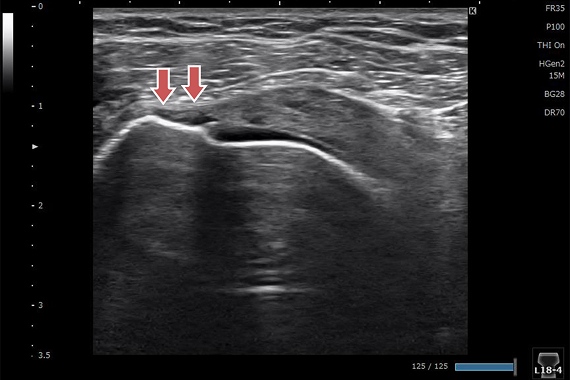

橈骨遠位端骨折

レントゲンでは分からない微小な骨折を認めます。